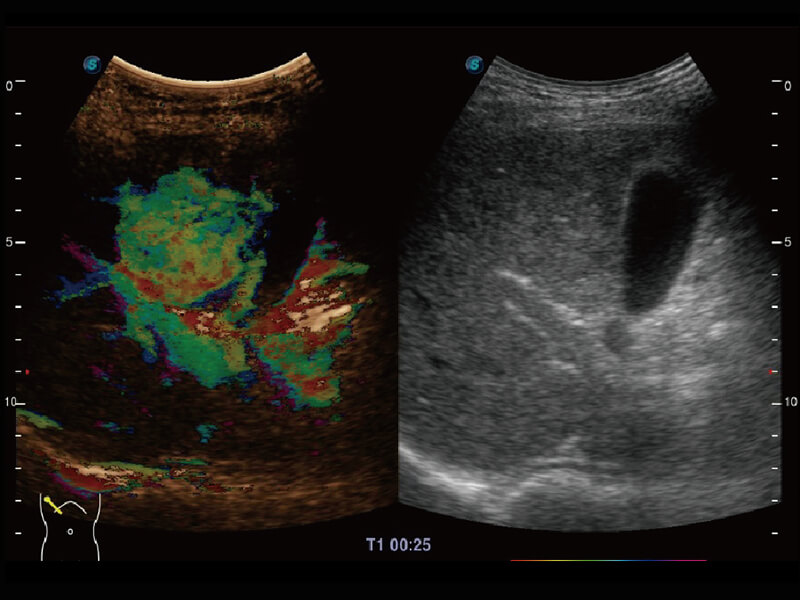

S60探头工艺,从前端信号处理每一个环节采集无损声学数据,真实还原组织原貌,再现解剖细节。

性能优异的硬件架构,极大提升超声系统的运行效率和数据处理能力。相比以往超声成像系统,Wis+平台为您带来极快的响应速度和成像帧频,提升检查流畅度。